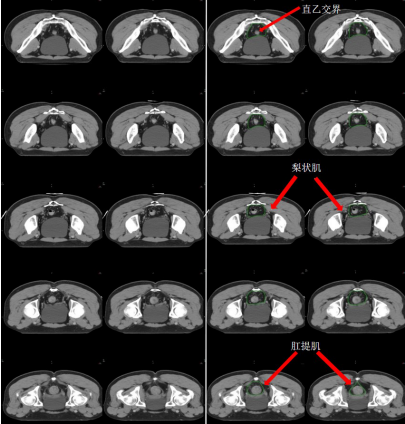

b) 直腸系膜區-M(深綠) (圖 7),邊界:

上界:腸系膜下動脈分叉為乙狀結腸動脈與直腸上動脈處/直乙交界;

下界:肛提肌插入外括約肌處/直腸周圍系膜脂肪組織消失處;

前界上:直腸上動脈前緣擴 0.7 cm;

前界中/下:直腸系膜筋膜,前方盆腔器官的后界;

后界:盆腔骶前區的前界;

外界上:側方、髂外淋巴結區的內側;

外界中:直腸系膜筋膜,側方淋巴結區的內側;

外界下:肛提肌內側緣。

圖 7 直腸癌直腸系膜區 CTV 勾畫示例

h) 肛門括約肌復合體-SC(桔色) (圖 13)邊界:

上界:肛提肌插入肛門外括約肌處/直腸肛管交界處;

下界:放松位的肛門緣;

前界、后界、內界、外界:肛門外括約肌圍成。

圖 12 直腸癌坐骨直腸窩 CTV 勾畫示例

圖 13 直腸癌肛門括約肌復合體 CTV 勾畫示例